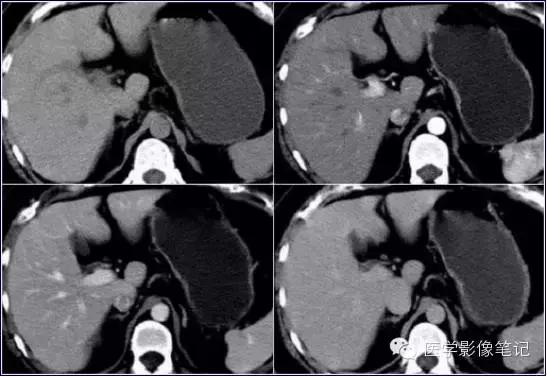

肝脏变异

獭尾肝/包围肝,见于5%的成人。

獭尾肝/包围肝

利德尔叶(Riedel’s Lobe)

肝的右下部向下如舌状突出生长的舌叶。

乳头状突

肝尾状叶结构,常误认为肿大淋巴结。

肝左叶缺如

右叶发育不全

内脏反转

咳纹肝

女性多见,由慢性咳嗽膈肌紧勒肝脏所致,也可见于过度束腰的妇女。

镰旁肝假病灶

多位于左叶内侧段或(和)左叶外侧段前缘镰状韧带旁。

机制:1、镰旁肝局部特殊血供因素;2、镰旁肝局部脂肪浸润。

来源:医学影像笔记